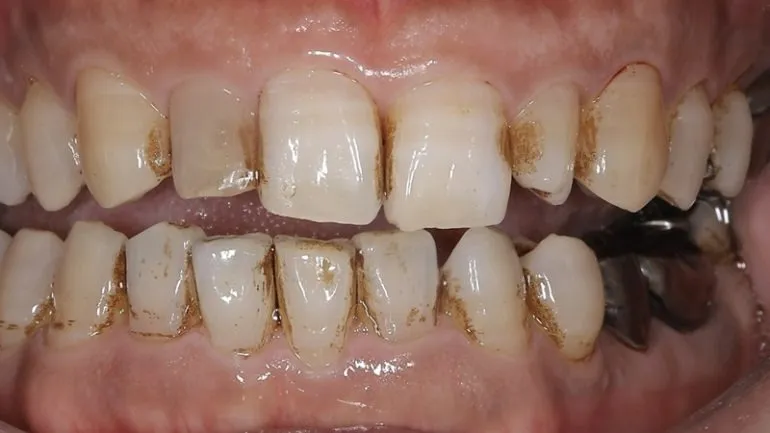

エアフローを使用したクリーニング

治療名

クリーニング

治療説明

治療回数

1回

副作用・リスク

呼吸器系の疾患や、薬剤によるアレルギー、妊娠・授乳期など、お身体の状態によってはエアフローが使用できない場合があります。

料金

保険適用

歯石がこびりついている場合も、保険適用でここまで綺麗になります。

最近歯医者さんに行けていない、または歯医者さんが怖いという方も、ぜひ一度ご相談ください。